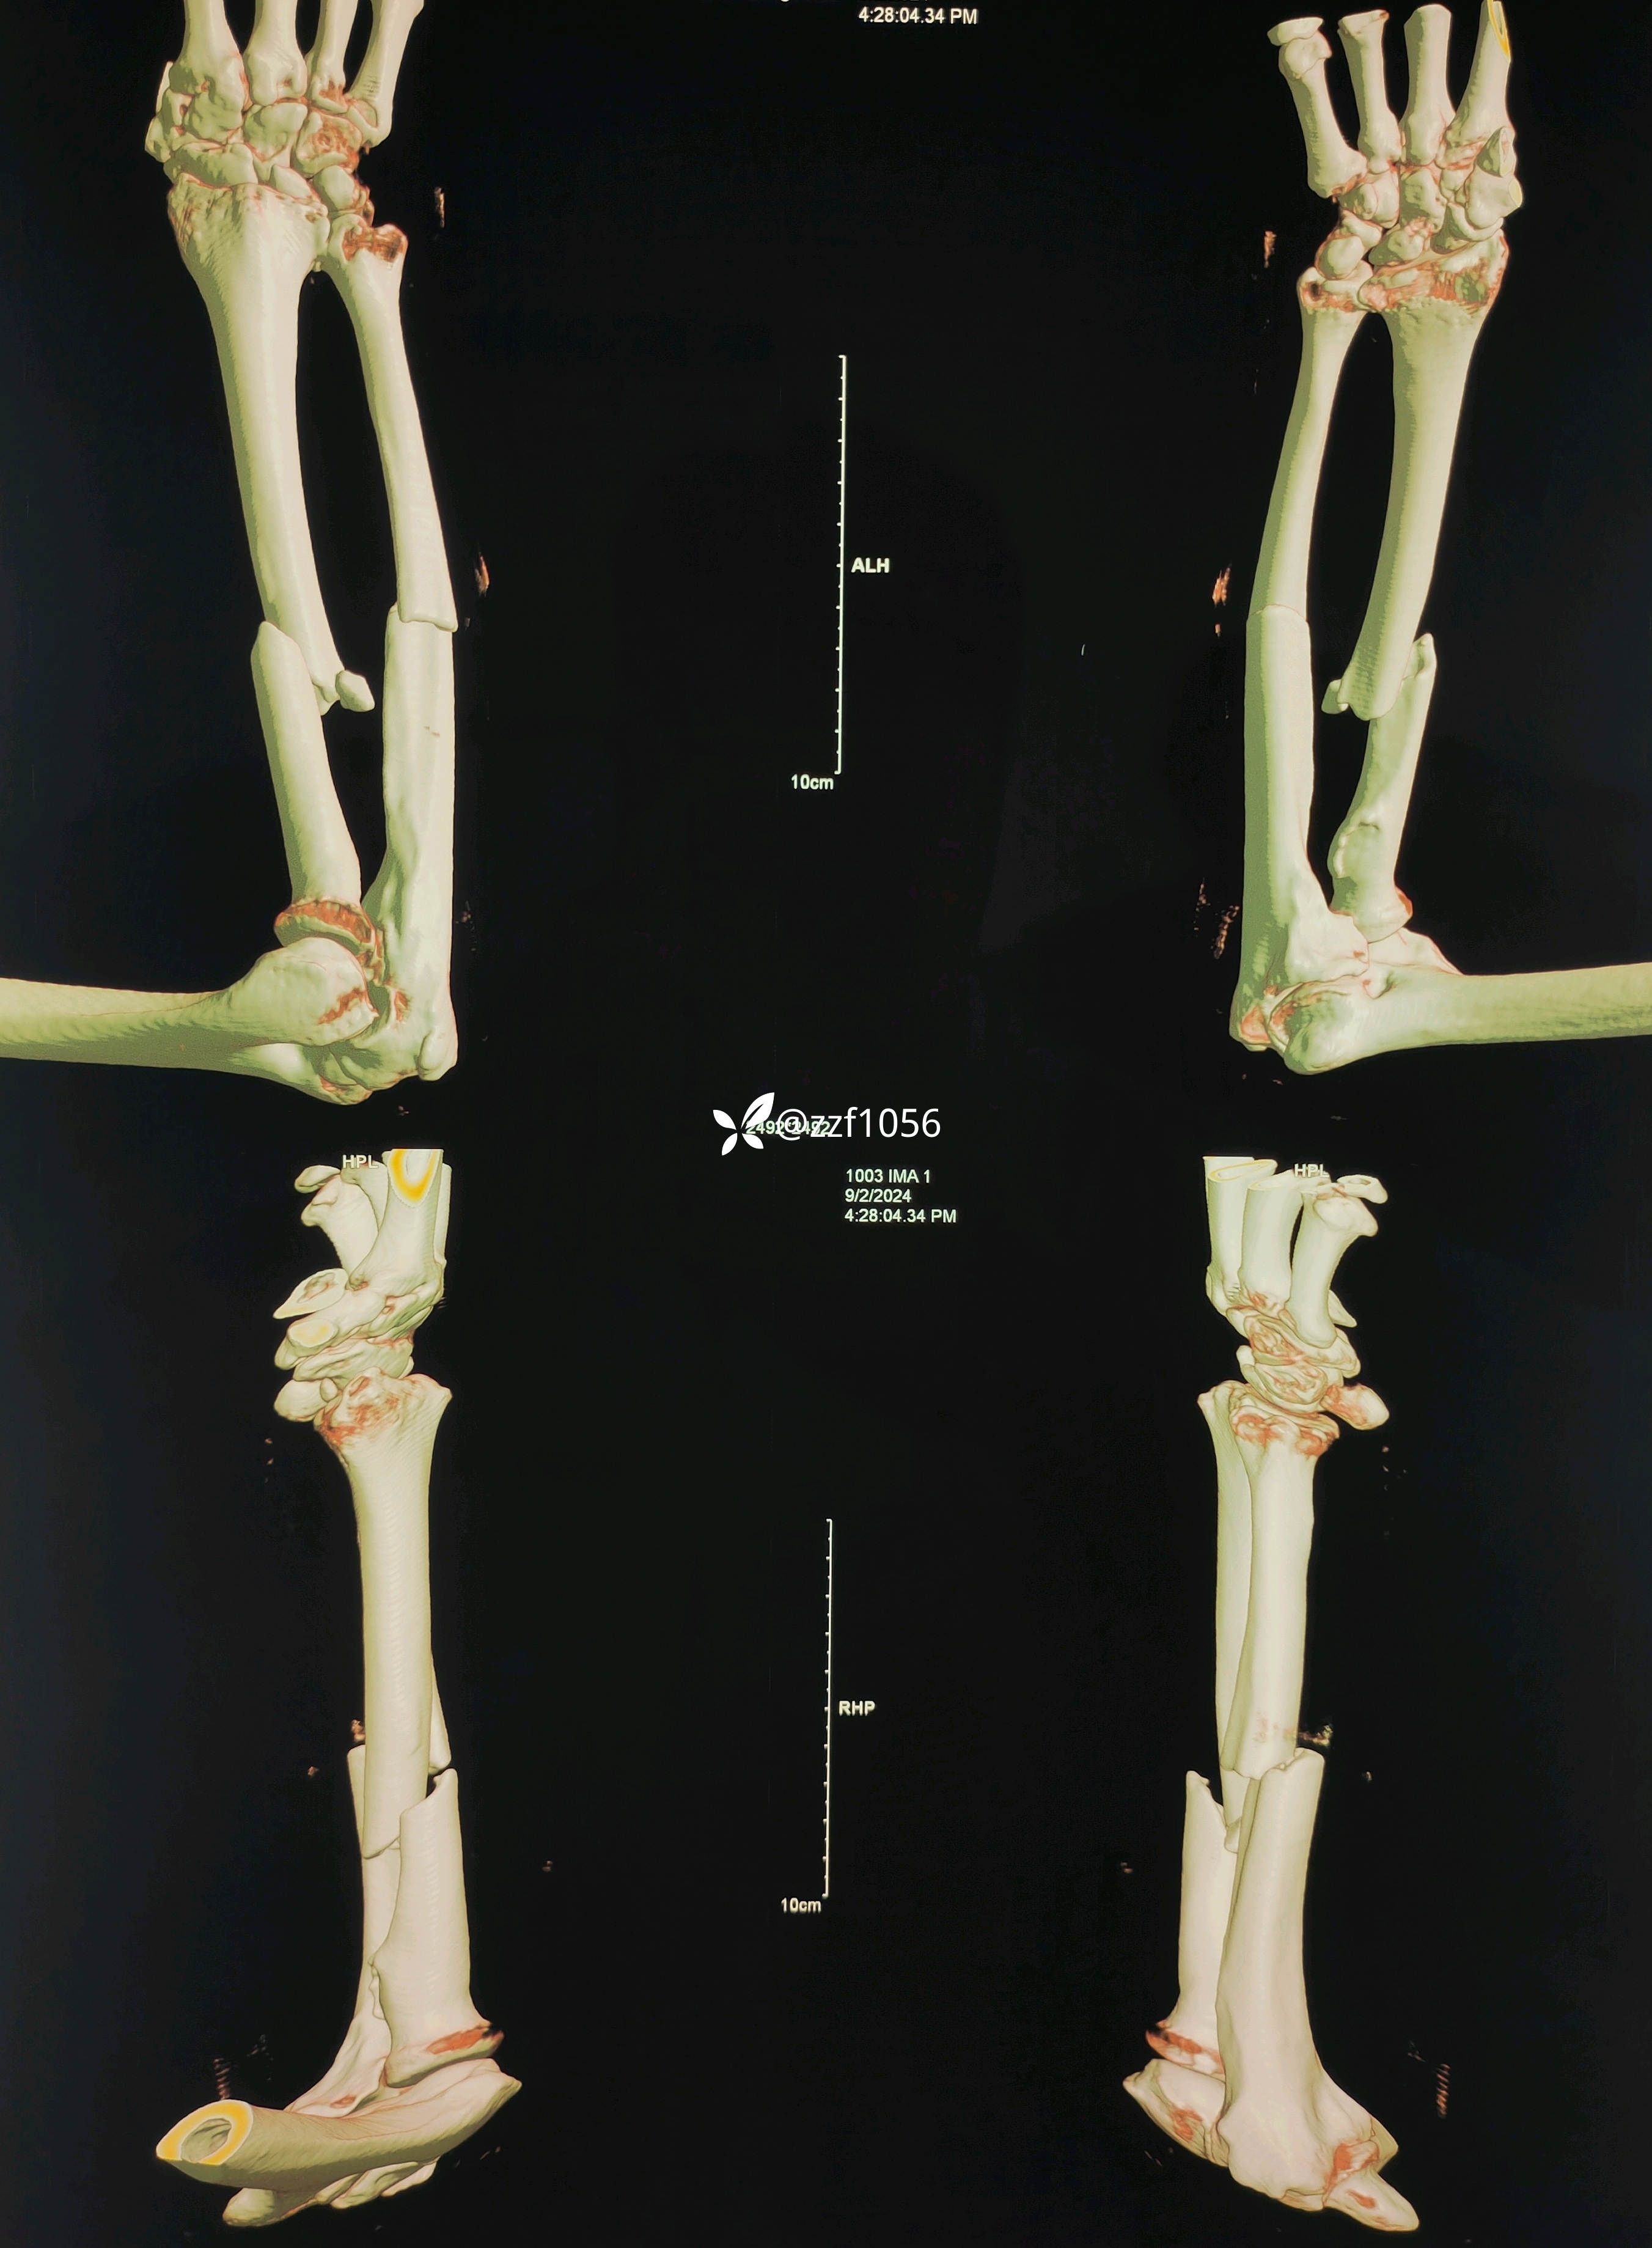

完善检查,第二天手术

原计划桡骨行掌侧Henry,仔细测量后改背侧Thompson。